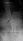

Eski Lomber Stabilizasyon Sistemi Altında Kırık (2)